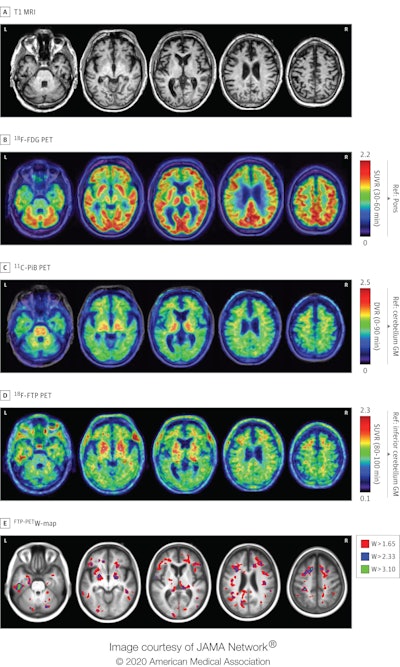

T1-weighted MR images (top row) demonstrate mild medial temporal and frontal atrophy. FDG-PET images (second row) show mild hypometabolism in the medial temporal, medial and dorsolateral frontal, and peri-insular regions, while the PiB-PET images (third row) were visually rated as negative for cortical retention. Flortaucipir-PET (fourth row) shows widespread patchy binding predominantly in the left greater than right frontotemporal areas. The flortaucipir-PET maps (bottom row) show that these focal increases are higher than what would be expected considering the patient's age. DVR: distribution volume ratio, GM: gray matter, Ref: reference region, and SUVR: standardized uptake value ratio with acquisition windows in parentheses. Images courtesy of JAMA Neurology and Mantyh et al.

Some four years before his death, he underwent an MRI scan, a PET exam with carbon 11-labeled Pittsburgh compound B (PiB), and a PET scan with flortaucipir. The results were later evaluated for abnormalities by readers who were blinded to the subject's autopsy data.

The flortaucipir-PET images showed radiotracer uptake spread about in a "patchy, frontotemporal-predominant pattern" that coincided with regions of neurodegeneration on MRI and hypometabolism on FDG-PET. Pathological results also confirmed the subject had stage IV CTE.